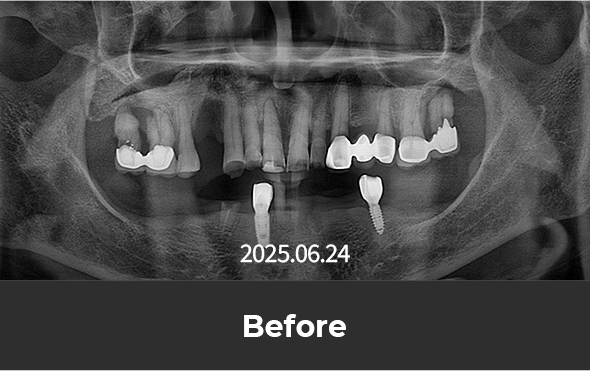

치료 후 사진

[ 환자분의 동의서 작성 후 게시하였습니다 ]